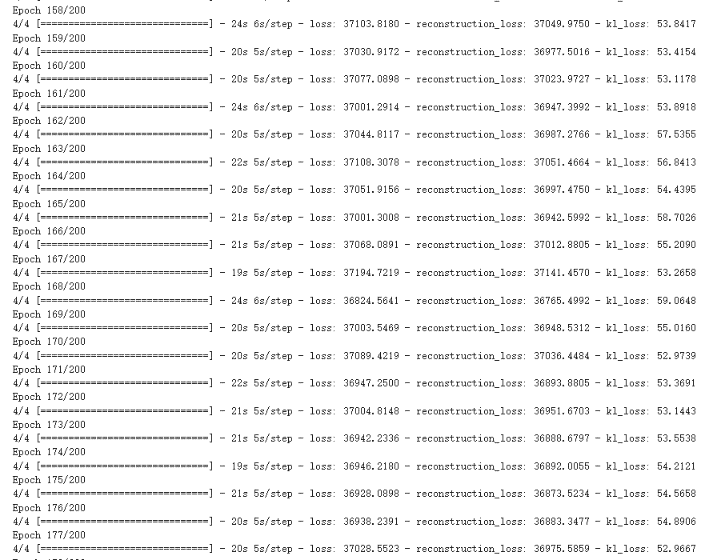

Figure 4. The training process of VAE.

For the lung cancer pictures generated by the VAE model, it can be found out by observing the picture Figure 2. The picture is more blurred than the original version. It can be observed that a lung cancer on the picture, but it basically can't see too many details. However, the VAE model generates images faster, and the average time to complete an Epoch is about 20 seconds (Figure 4), and it can be mass-produced quickly.

Training and Generation Time. VAE: The VAE model's training efficiency was evident. With 200 epochs, the average time per epoch was roughly 20 seconds, as indicated in Figure 4. This brisk training, coupled with its faster image generation speed, implies that the VAE could be advantageous in scenarios demanding rapid image production.